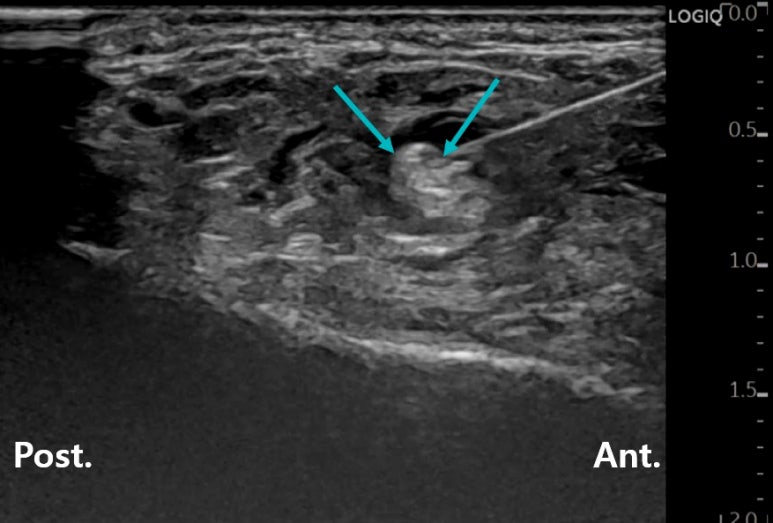

초음파 약침

화살표로 표시한 신경 압박 부위가

한의학에서는 '족소음경근'의 혈자리에 해당하는데요.

손으로 꼼꼼하게 문제가 있는 곳을 찾아서

초음파로 보면서 염증 유착 부위를 풀어주고요.

조직 재생에 효과적인

PDRN 연아약침이라는 DNA 주사로

아래쪽에 이어서 위쪽까지도 유착을 떼어냅니다.